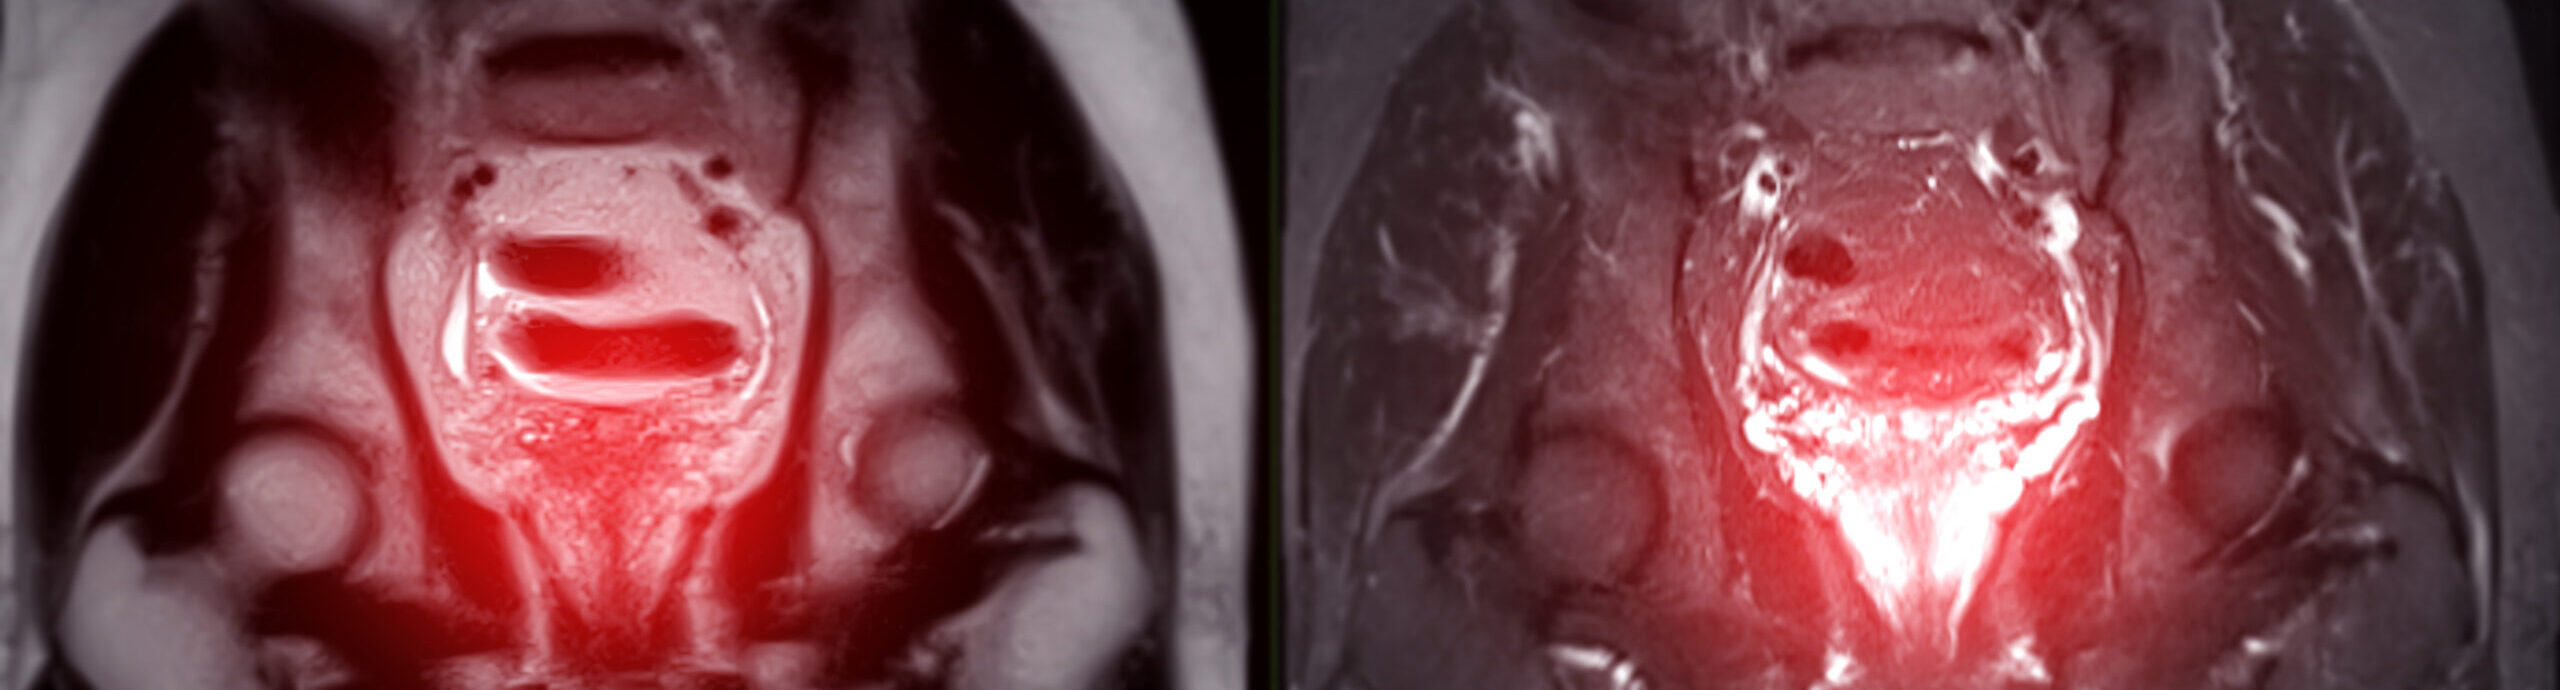

In der Vitus Privatklinik werden fortschrittliche bildgebende Verfahren eingesetzt, um ein Rezidiv umfassend zu beurteilen. Dazu gehört die MRT zur Beurteilung der lokalisierten Erkrankung und die PSMA-PET/CT mit Gallium-68 zum Nachweis von Metastasen im ganzen Körper.

Gemeinsam ermöglichen diese Verfahren eine präzise Bestimmung des Ausmaßes des Rezidivs und eine individuelle, fallbezogene Therapieplanung.

- Befunde aus MRT- und PSMA-PET-Bildgebung: Moderne Bildgebung hilft zu bestimmen, wo sich das Rezidiv befindet und wie es sich verhält, und unterstützt die Entscheidung zwischen einer einzelnen fokalen Behandlung oder einer umfassenderen Strategie.